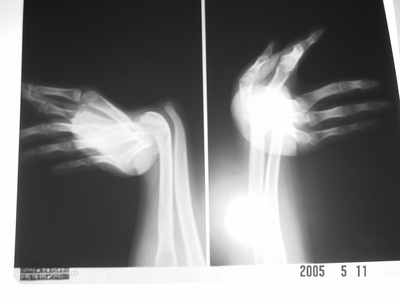

手关节弯曲畸形